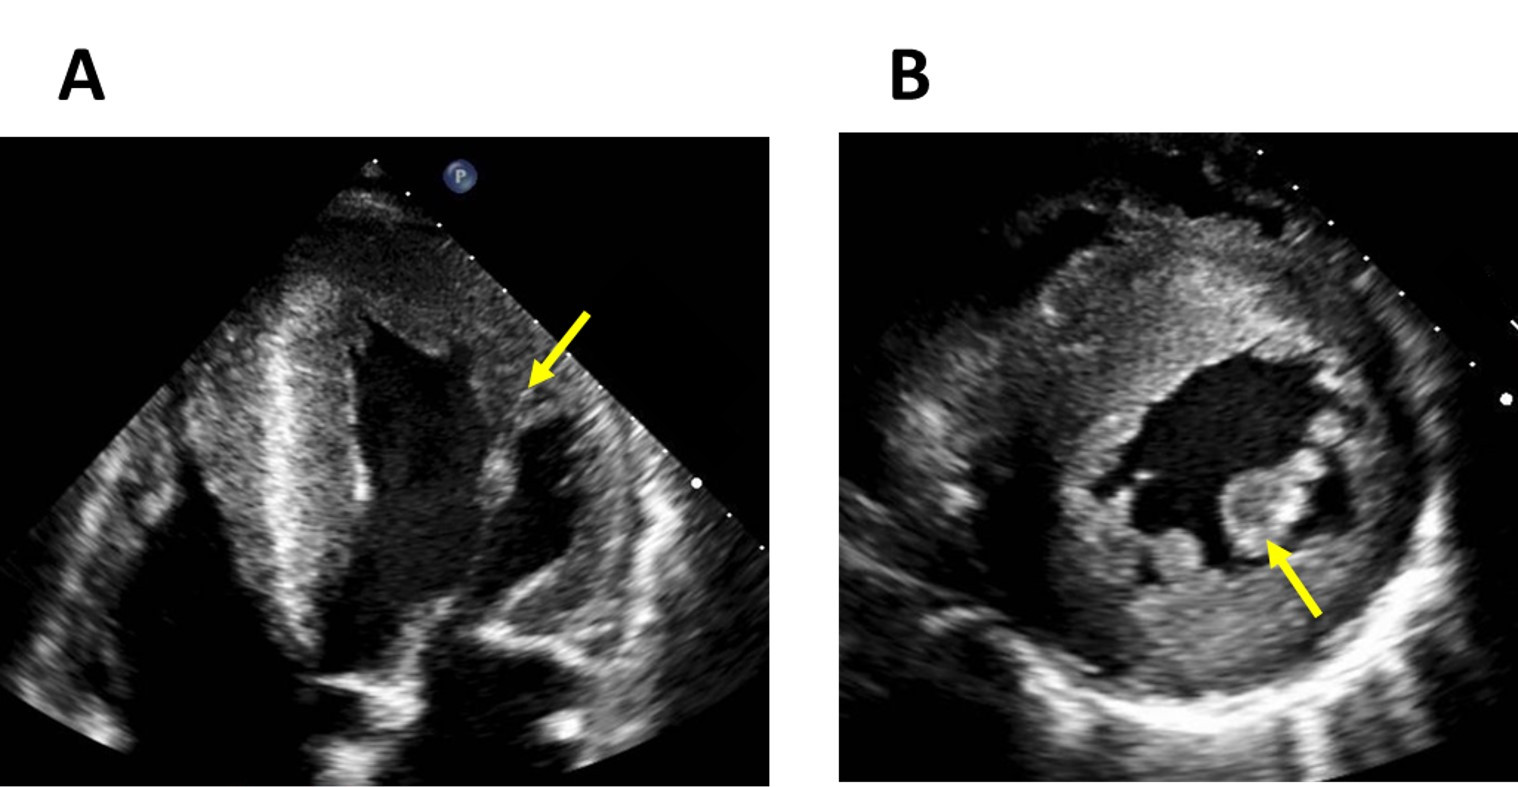

LVH in FD typically presents a concentric pattern (Fig. 2) without resting left ventricular outflow tract obstruction (LVOTO). However, obstructive forms, asymmetric septal (Fig. 3), apical and eccentric hypertrophy have also been described [19, 20]. In fact, LVOTO may be more prevalent and have a greater impact on symptoms than was previously thought. In a small cohort of 14 patients, LVOTO was revealed by exercise stress echocardiography in six patients with refractory symptoms [21]. A smaller cavity size and papillary muscle (PM) hypertrophy were speculated to be involved in the LVOTO.

Fig. 3.Asymmetrical septal hypertrophy mimicking hypertrophic cardiomyopathy in a patient with Fabry disease. Long-axis (A) and short-axis (B) CMR images and an echocardiography apical four-chamber view (C) of a patient with Fabry disease showing an asymmetrical septal hypertrophy that mimics the pattern seen in hypertrophic cardiomyopathy.